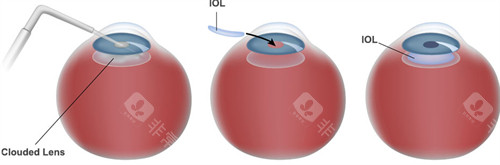

人工晶体置换需通过角膜切口将人工晶体植入眼内,若术中无菌操作不严或术后护理不当,细菌可能通过切口侵入眼内,引发眼内炎。

人工晶体依赖周边囊袋固定,若术中囊袋撕裂、术后剧烈运动或眼部受到外力撞击,晶体可能发生偏移或脱位。

人工晶体度数需根据术前角膜曲率、眼轴长度等参数计算,但个体差异可能导致计算偏差。

人工晶体置换术虽存在潜在风险,但仍是目前治疗白内障、高度近视的有效手段。

手术决策需综合考量眼部条件、全身健康状况及个人需求。对于高度近视患者,若角膜厚度不足无法接受激光手术,ICL晶体植入仍是优选;对于白内障患者,人工晶体置换是改善视力的仅有途径。